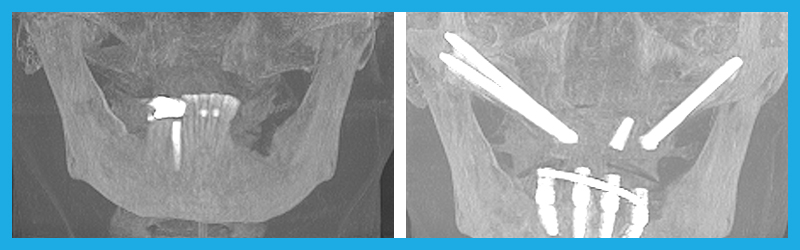

Before and After

Zygomatic Implants